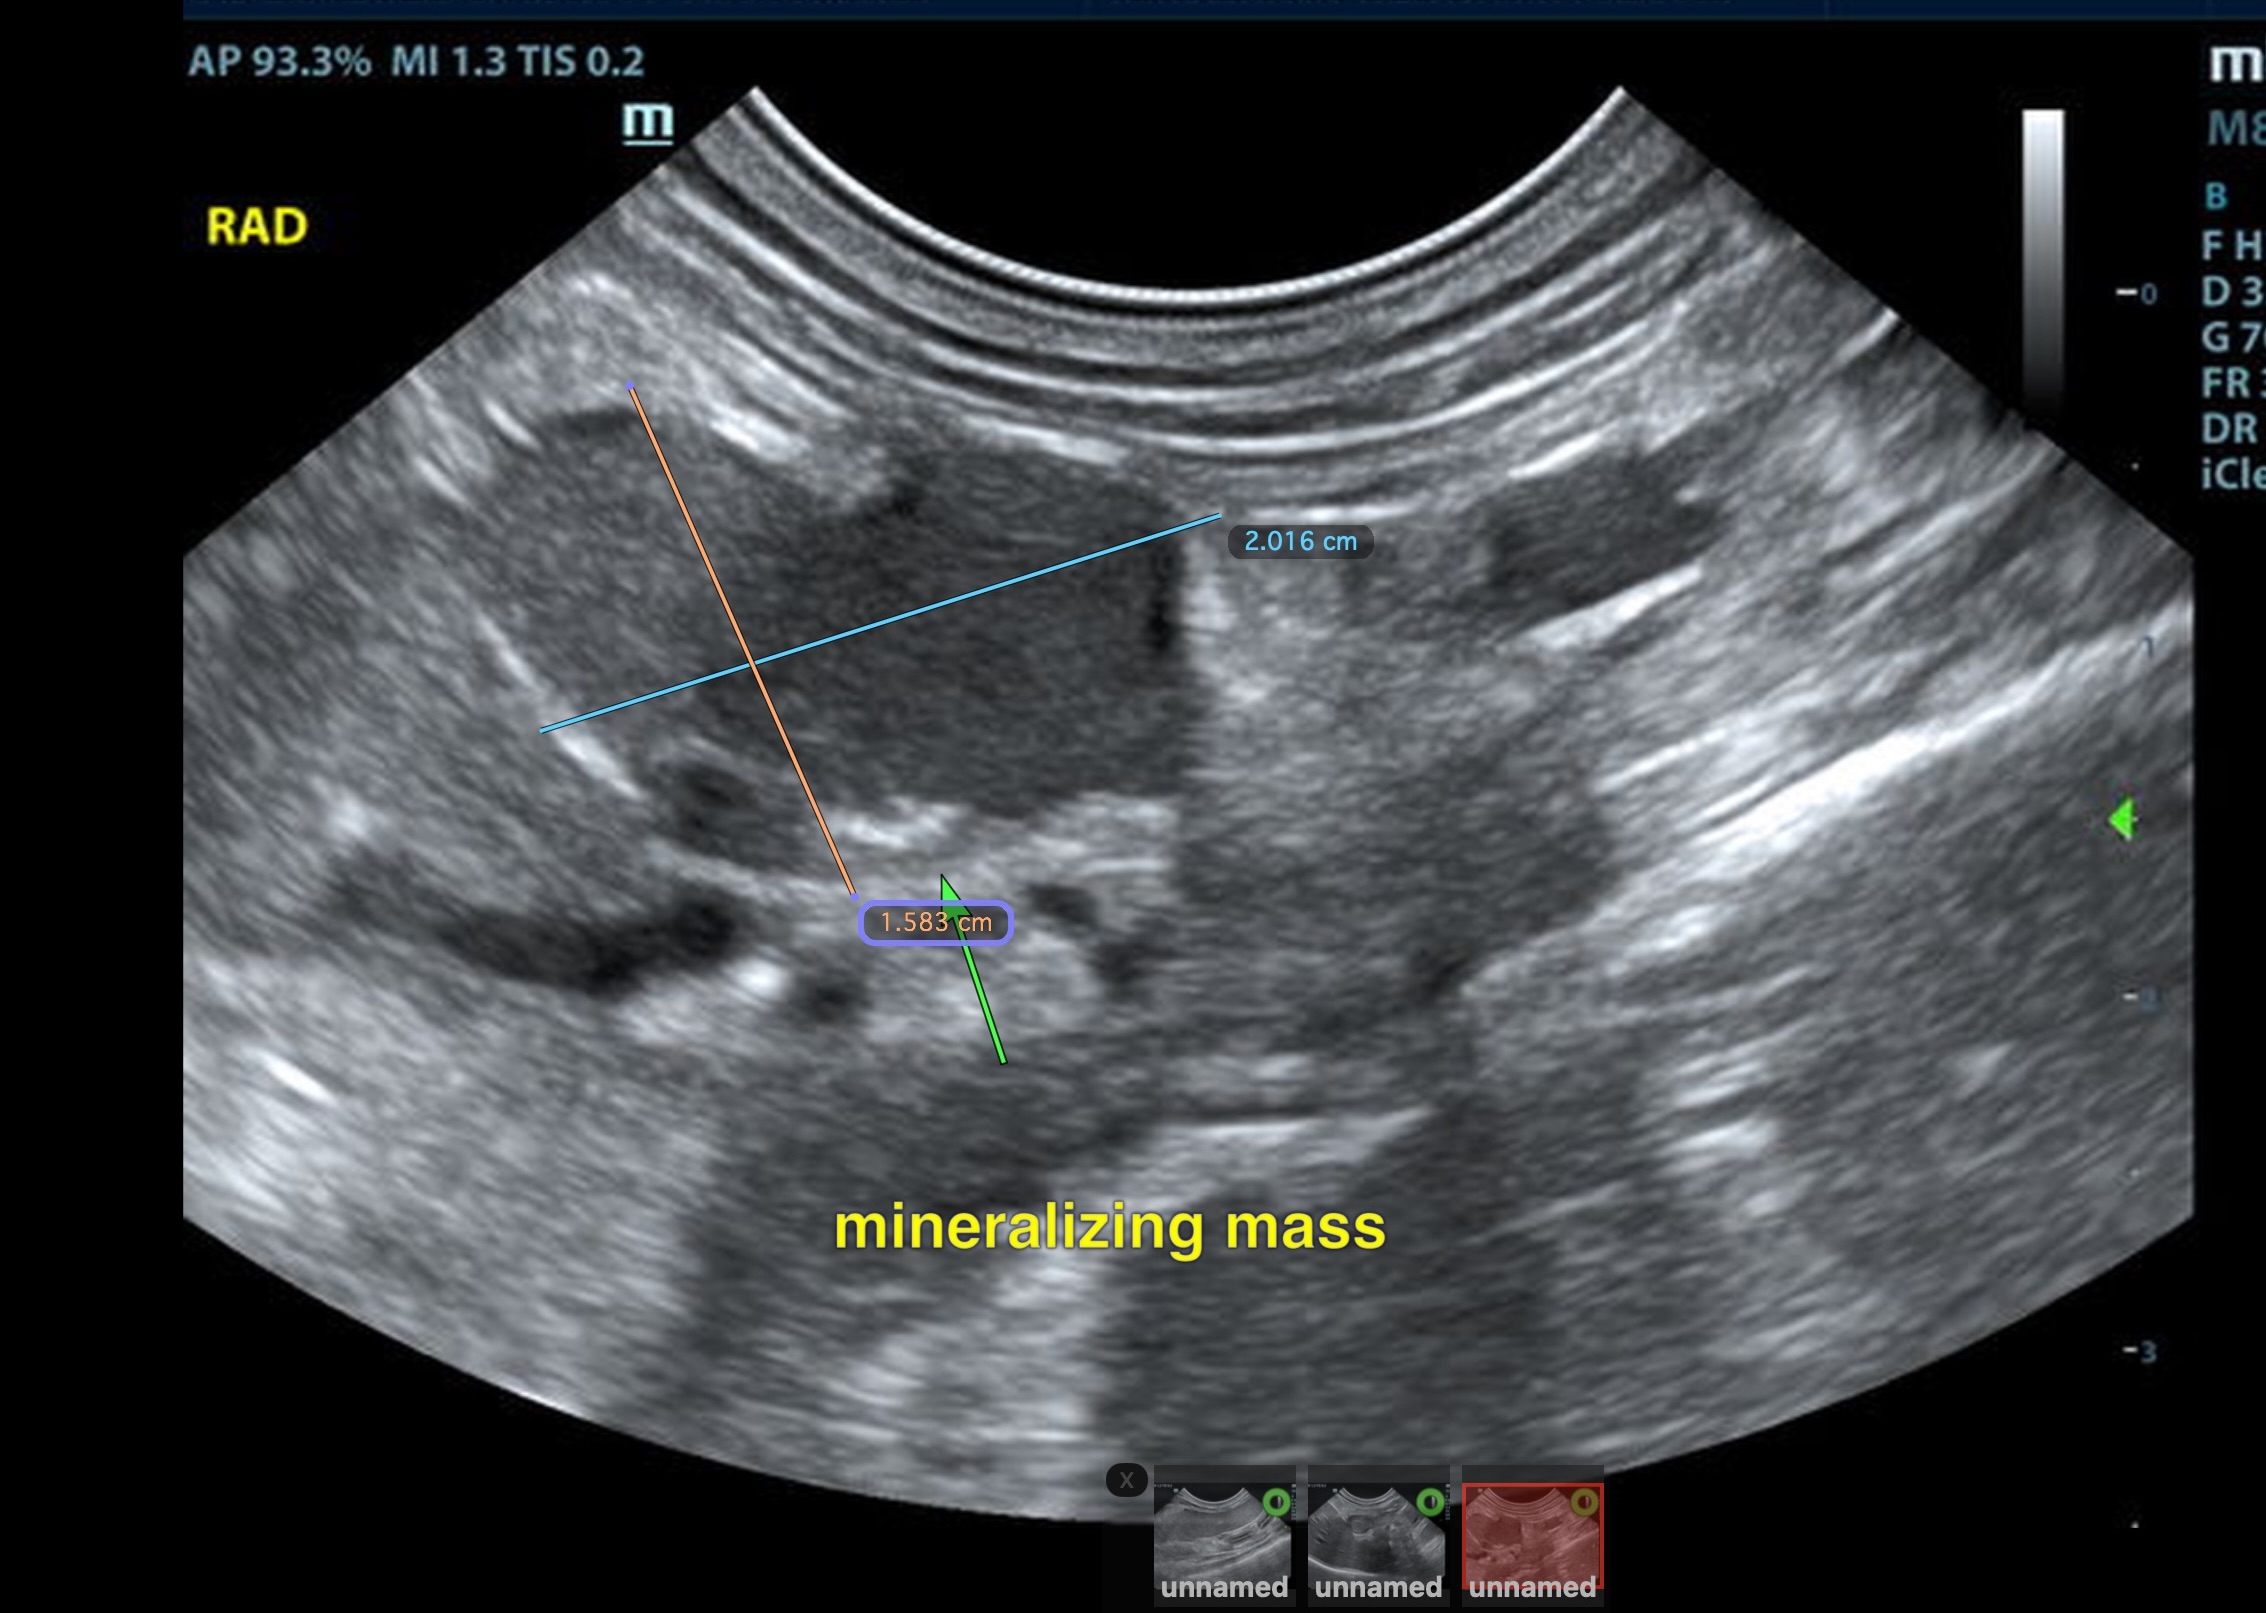

The left adrenal gland was visualized and recognized as normal for this breed. The left adrenal gland measured 0.7 c 0.35 cm. The region of the right adrenal gland revealed a mineralizing mass that impinged upon the vena cava and appeared to be occupying the phrenic vein; it measured 2.2 x 1.2 cm. This appears to be isolated. Normal right adrenal gland was not found.

Given the sodium potassium ratio is normal, it is unlikely that this is an aldosterone producing tumor.  However, carcinoma and pheochromocytoma are possible. Serial blood pressure measurements are warranted. Surgical consultation is recommended. Screening 25g FNA of the spleen can be considered if weight loss has occurred to ensure that it is a reactive spleen given its minor enlargement; however this could also be justified by sedation as the changes are relatively subtle. CT evaluation for surgical planning would be ideal.